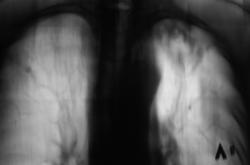

Пациент находится на диспансерном учете в туб. кабинете, по поводу инфильтративного туберкулёза верхней доли левого лёгкого, получает специфическое лечение. Пациент направлен в рентгеновский кабинет для рентгенологического исследования исследования органов грудной полости "в динамике". Проведено стандартное исследование.

Для сравнения приводятся изображения, произведенные чуть больше года тому.